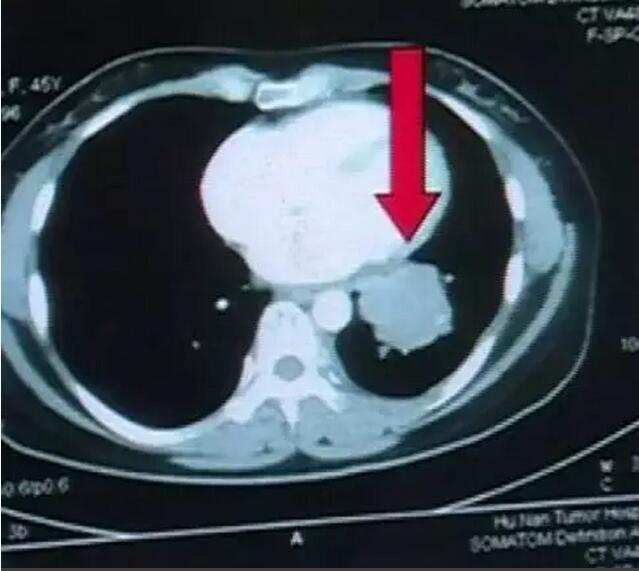

易女士在左下肺部有一個(gè)大的腫塊,我們經(jīng)過一個(gè)多月的放療之后,前兩天復(fù)查了CT ,復(fù)查之后,原來在左下肺的病灶 ,現(xiàn)在就完全不見了。